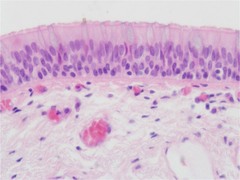

pseudostratified

protection, movement of mucus via cilia, and secretion

found in: nasal cavity, walls of respiratory passageways